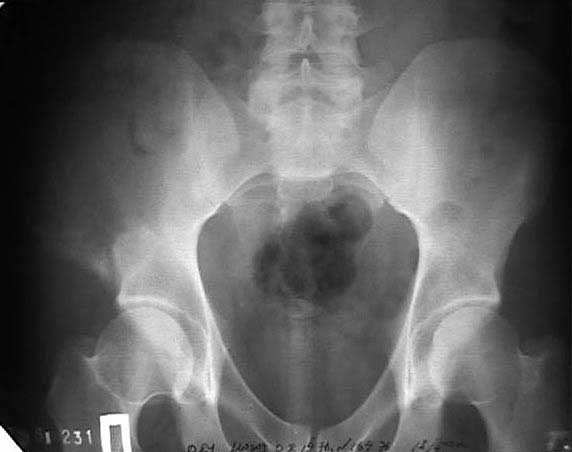

В 2002 году буквально "промелькнул" и исчез пациент с подобным остеолизом. Обследован (биопсия ) в отделении костной онкологии, а затем у дерматологов. Причиной остеолиза признан актиномикоз. К сожалению в то время не удалось выполнить КТ, а рентгенограммы не качественные - в приложении.